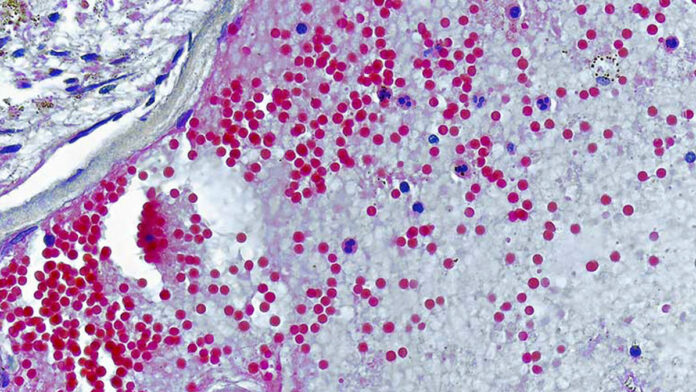

El virus de la viruela del mono registra más de 40.000 casos confirmados en países donde esta enfermedad había sido erradicada. Entre estos países se encuentra Chile, donde se han registrado 450 casos confirmados al 1 de septiembre de 2022. Después de que la Organización Mundial de la Salud declarara la viruela del mono como una emergencia de salud pública de importancia internacional, y que el Ministerio de Salud decretara Alerta Sanitaria hasta el 30 de septiembre por esta enfermedad, es importante tener información para protegernos a nosotros mismos y a nuestros seres queridos.

El número de casos confirmados de viruela del mono en Chile llegó a 450, según el último reporte del Ministerio de Salud. Esta cifra lleva a revisar la información disponible sobre este virus. Jorge Osorio, integrante de la Coalición de Defensa contra la Pandemia de Abbott, aclara los conceptos erróneos más comunes.